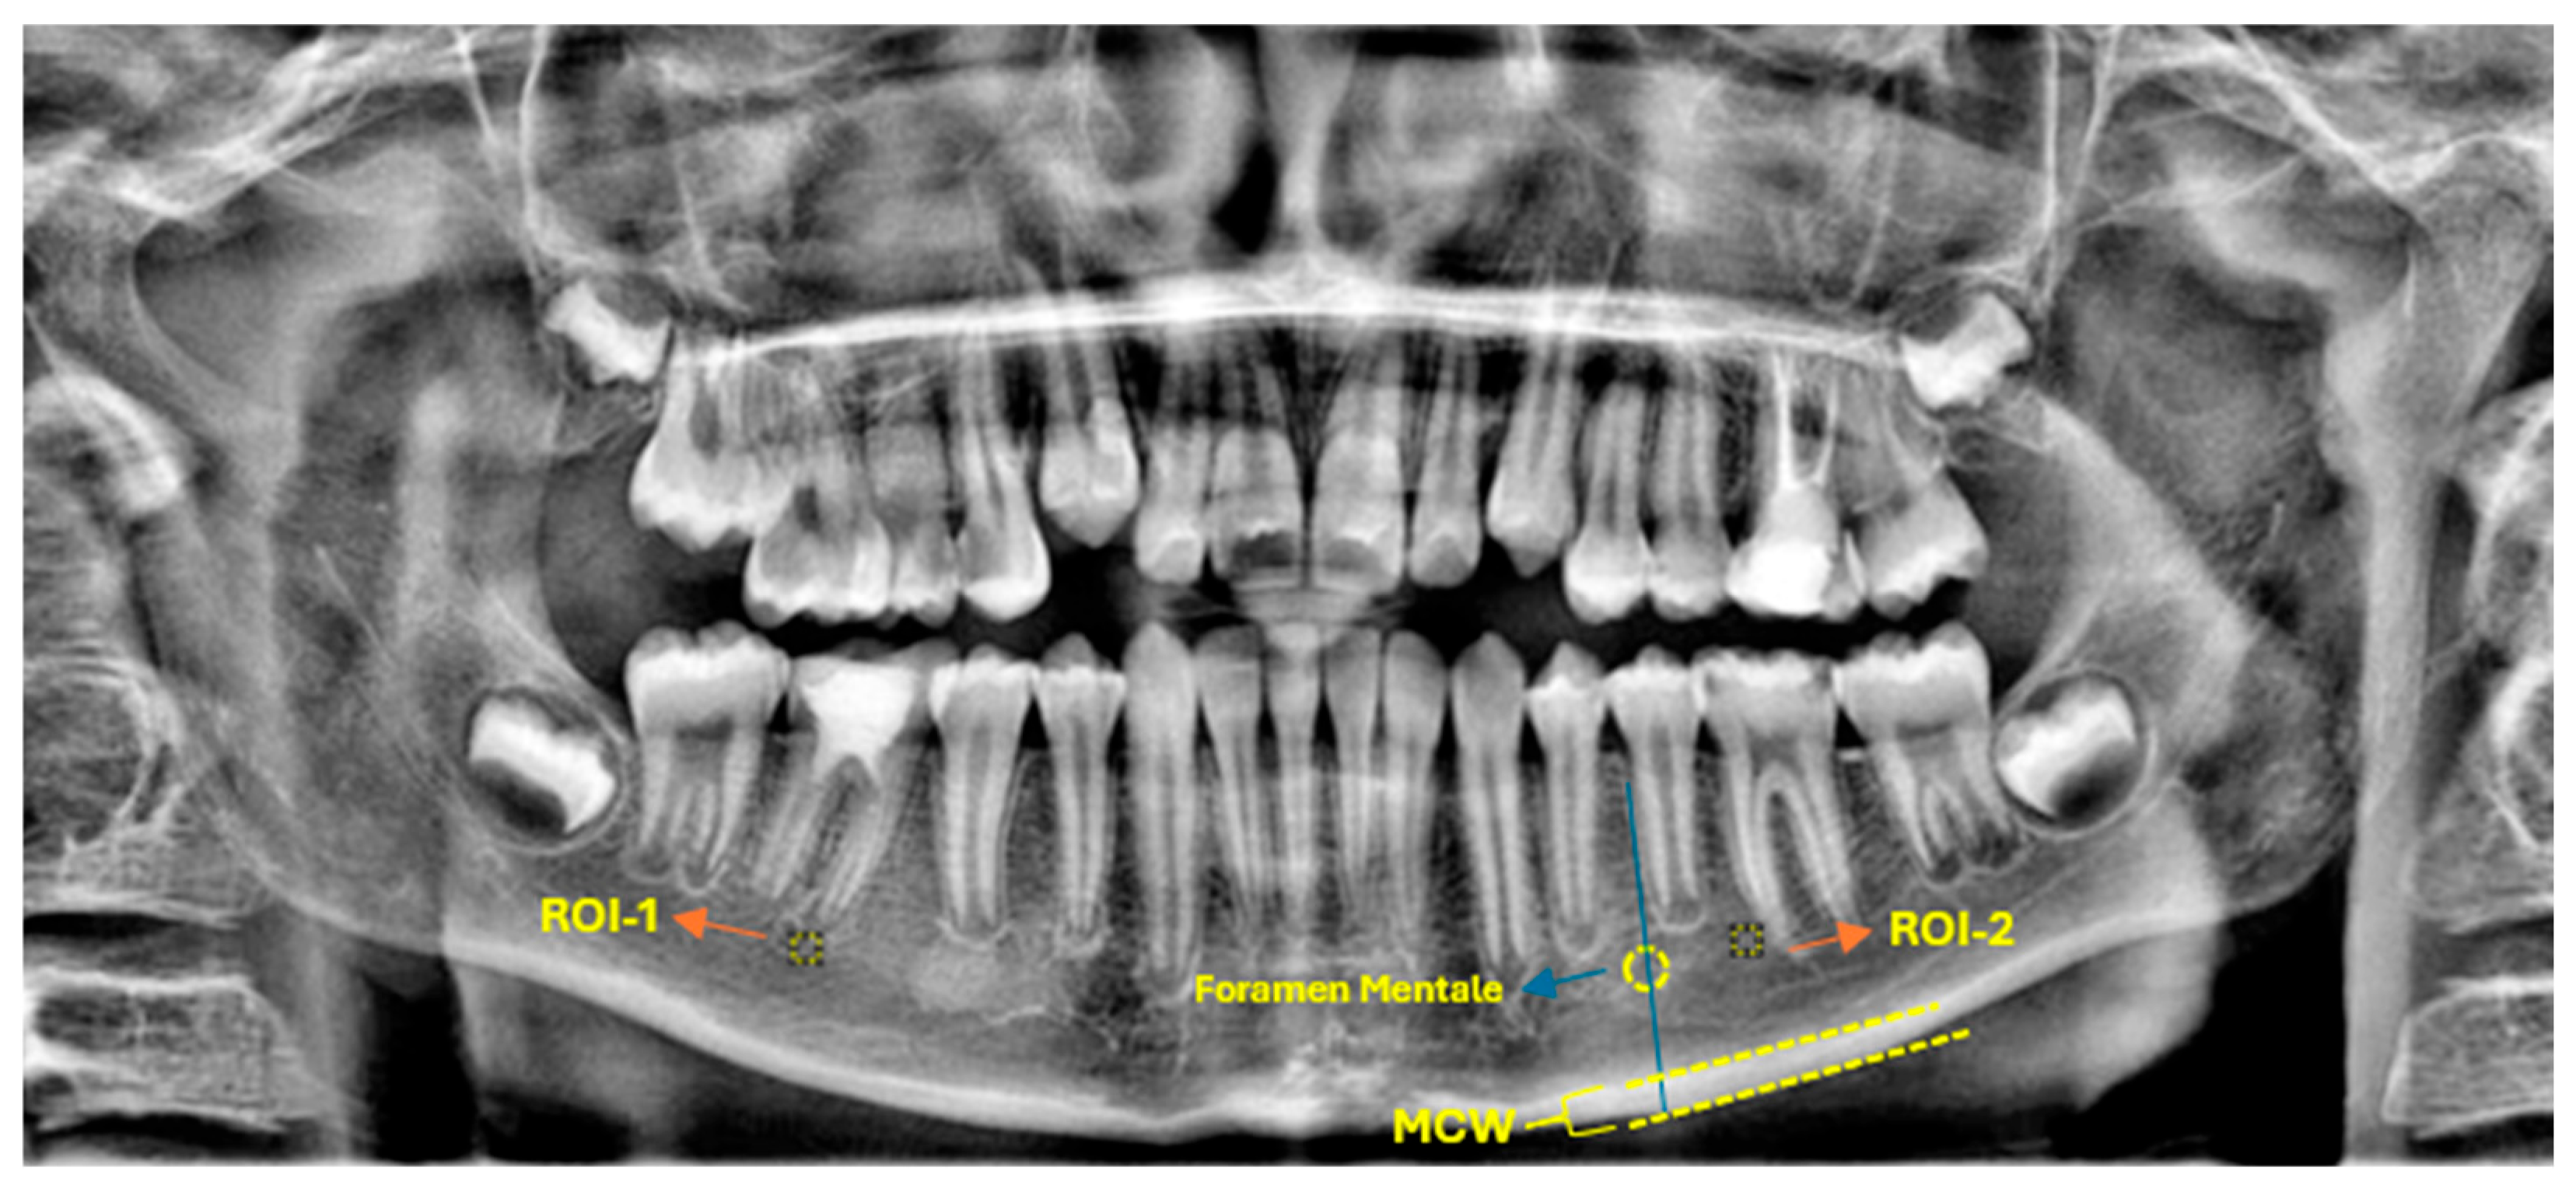

3.3. Radiographic Assessment of Periapical Status (PAI)

At baseline, 37 out of 40 individuals (92.5%) presented with PAI scores ≥ 3, indicative of existing apical pathology. At the 6-month follow-up, all patients demonstrated radiographic healing, with 33 individuals (82.5%) exhibiting a PAI score of 1, and the remaining 7 individuals (17.5%) showing a PAI score of 2. Importantly, no cases retained PAI scores ≥ 3. This marked improvement was statistically significant, as corroborated by the Pearson chi-square test (χ2(3) = 67.72, p < 0.001) and the Linear-by-Linear Association test (p < 0.001), thereby providing robust evidence for the radiographic resolution of apical lesions following regenerative therapy. Table 4 illustrates the PAI score distribution and statistical analysis results.

Figure 6. Series of periapical radiographs illustrating two separate clinical cases. (a) Pre-operative radiograph of the first case showing a distinct periapical radiolucency corresponding to a PAI score of 4. (b) Six-month follow-up of the first case demonstrating significant periapical healing, with the PAI score reduced to 2. (c) Pre-operative radiograph of the second case presenting a large periapical lesion, also corresponding to a PAI score of 4. (d) Six-month follow-up of the second case showing complete resolution of the lesion, with the periapical area appearing healthy and achieving a PAI score of 1.